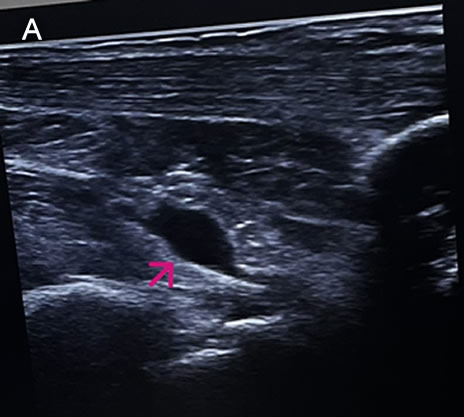

![]() History: A 73-year-old female patient with a past medical history of arterial hypertension presented with a 2-month history of polyarthralgias and subjective fever. Two months before admission, while in Santa Cruz, Bolivia, the patient began experiencing a subjective fever accompanied by chills. One day following symptom onset, she developed severe joint pain involving both wrists, shoulders, and ankles. Two days later, she reported decreased appetite, nausea, vomiting (4–5 episodes per day), and watery diarrhea (6–7 episodes per day). On day 3 of illness, the patient developed localized swelling over the dorsum of the right foot. She received symptomatic treatment with minimal pain relief. One month before admission, the patient experienced severe upper limb pain, which impaired her ability to raise her arms or hold objects, along with intense ankle pain that significantly limited walking. She was evaluated at the rheumatology service and subsequently referred to our outpatient clinic. Epidemiology: The patient was born and currently resides in Lima. She currently has no occupation. She traveled to Santa Cruz, Bolivia, from March to June of the present year to visit her son. There, she reports visiting many tourist attractions, including areas of the highlands and the jungle, where she sustained numerous mosquito bites. Physical Examination on admission: BP: 130/80, RR: 18, HR 87, SpO2: 97% on room air. Musculoskeletal examination revealed tenderness on palpation of the metacarpophalangeal joints, decreased grip strength, and pain with passive and active movement of both shoulders. Additionally, tenderness was noted on palpation of the popliteal region, both knees, and both ankles. The patient presented with difficulty walking due to persistent pain. The rest of the exam was non-contributory. Laboratory: Hemoglobin 12.9g/dL, Hematocrit 36.2%, Platelets 222000, WBC 4500, /µL; with bands 1%, neutrophils 49%, eosinophils 5%, basophils 0%, monocytes 0%, lymphocytes 45% Glucose 88 mg/dl, Urea 42 mg/dl, total proteins 7.15 g/l, albumin 4.07 g/l. The urine exam was normal. An Ultrasound examination demonstrates bilateral synovitis involving the wrist joints and popliteal regions, characterized by joint effusion and synovial thickening. Additionally, there is evidence of bilateral tenosynovitis of the Achilles tendons, characterized by hypoechoic peritendinous fluid and thickening of the synovial sheath. Evaluation of the hindfoot reveals retrocalcaneal bursitis, manifested by distention of the retrocalcaneal bursae with anechoic fluid (IMAGE A, see arrow). UPCH Case Editors: Carlos Seas, Course Director / Paola Nakazaki, Associate Coordinator |

Discussion: The skin scrape microscopy shows structures typical of Sarcoptes scabiei. An ELISA test for detecting IgM antibodies against the Chikungunya virus was positive. Chikungunya virus is an arthropod-borne alphavirus in the Togaviridae family, transmitted by mosquitoes, mainly Aedes aegypti and Aedes albopictus. It was first identified in East Africa during the 1950s. It was called kungunyala, meaning “to walk bent over” or “to become contorted,” due to the severe pain often associated with the illness (1). Chikungunya is now widespread across tropical and subtropical regions of Africa, Asia, the Americas, and, to a lesser extent, Europe, primarily through travel-related cases (2). The incubation period typically ranges from 2 to 6 days. Less than 15% of infected individuals remain asymptomatic. At the same time, most individuals develop symptoms, typically starting with fever and malaise, which can be accompanied by musculoskeletal manifestations that may even precede fever, such as arthralgias and myalgias, or dermatologic involvement. In most cases, this includes an erythematous maculopapular rash that primarily affects the trunk but can also extend to the face and extremities (3). Arthralgias are usually bilateral and more often affect distal joints, with hands, wrists, and ankles being the most commonly involved areas. They may also be accompanied by tenosynovitis or periarticular swelling. The acute phase typically lasts between 1 and 2 weeks, characterized by a high-grade fever that typically lasts for three to five days. Musculoskeletal symptoms may persist chronically in around 30% of cases (4,5). Less common manifestations include lymphadenopathy, pruritus, and gastrointestinal symptoms, which can appear after viremia has resolved (3). Chikungunya infection should be clinically suspected in patients with epidemiologic exposure, considering the differential diagnosis of other conditions such as dengue fever, oropouche, Zika virus, leptospirosis, malaria, and rheumatoid or reactive arthritis. The diagnosis is established by PCR detection of chikungunya viral RNA, especially in those who present within the first week of symptom onset, or by serology in patients with symptoms lasting more than one week. ELISA can detect IgM within five days of symptom onset and can persist for weeks to months (3,6). There is no specific antiviral treatment for chikungunya virus infection. Management is supportive and symptomatic. The main aspects of therapy include rest, proper hydration, and relief of fever and joint pain with acetaminophen. NSAIDs can be used for persistent arthralgia after confirming dengue has been ruled out. For patients who develop chronic arthritis or arthralgias, corticosteroids and certain antirheumatic drugs, such as methotrexate, have been effective in small, randomized trials and observational studies (7,8). Currently, there are two approved vaccines: a live-attenuated vaccine (IXCHIQ) indicated for adults 18 and older, and a virus-like particle vaccine (Vimkunya) for individuals 12 and older. Protection against infection is 40%, and against disease is 70%. The vaccines are mainly recommended for travelers and laboratory workers; they are also used in areas where outbreaks have been identified. The IXCHIQ has caused serious adverse events in people 60 and older. The FDA, CDC, and EMA have ceased their indication for that age group, and the WHO has taken a cautious stance. Our patient sought care at our Institute after 2 months of symptom onset due to persistent pain that caused difficulty walking (VIDEO A), decreased grip strength (VIDEO B), and impacted her ability to perform daily activities. She is part of the subset of patients who continue to have chronic musculoskeletal involvement. She received symptomatic treatment with orphenadrine and celecoxib, and a drainage procedure was performed on the fluid in the retrocalcaneal bursae, as previously described in the ultrasound, with reported pain improvement at the follow-up visit. References |